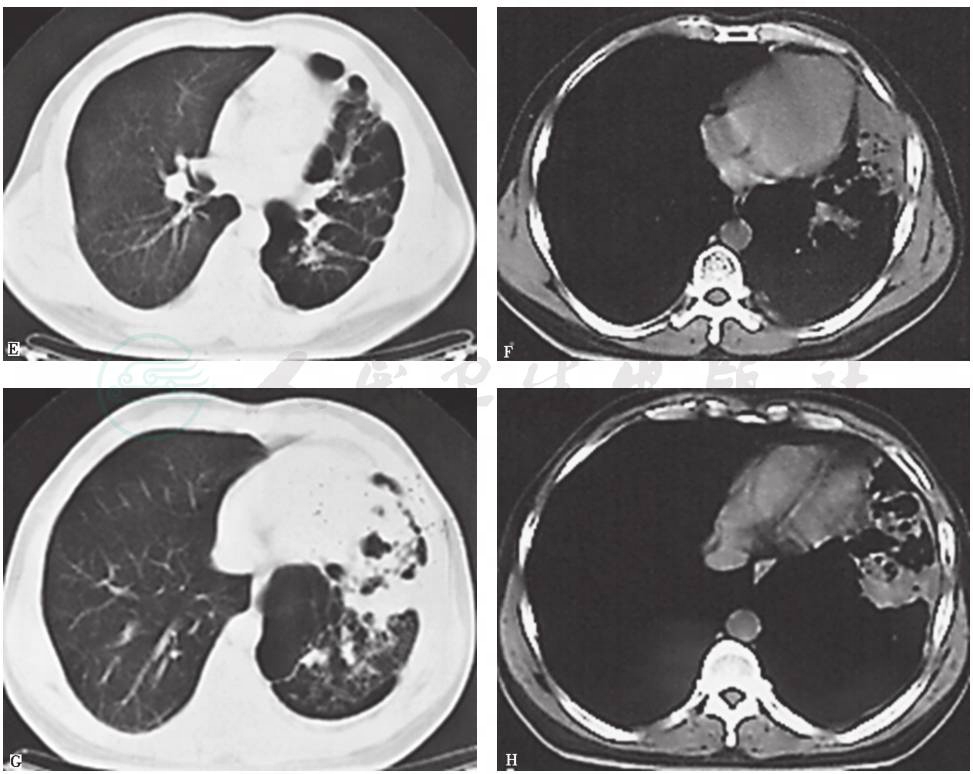

图7 6年半前胸部CT表现

胸部CT可见左主支气管被高密度钙化灶阻塞进一步加重,但左上肺体积增大含气增多,左下肺略缩小伴局限性斑片状高密度病灶和膨胀不全;右肺代偿性含气增多;左侧胸膜弥漫性病变减轻

图8 4年半前胸部CT表现

胸部CT可见左主支气管被高密度钙化灶阻塞进一步加重,管腔几近完全阻塞,左肺体积略缩小伴局限性不张,左上肺代偿性肺气肿和肺大疱进一步加重;右肺代偿性含气增多;未见左侧胸膜病变

图9 2年半前胸部CT表现

胸部CT可见左主支气管被高密度钙化灶管腔几近完全阻塞,左上肺代偿性肺气肿和肺大疱进一步加重,左下肺体积略增大伴多发肺大疱,并见左下肺前内基底段实变;右肺代偿性含气较前有所减轻

图10 1年前胸部CT表现

胸部CT可见左主支气管病灶同前,左上肺代偿性肺气肿和肺大疱进一步加重,左下肺多发肺大疱增多,左下肺前内基底段实变仍存在;右肺代偿性含气未见加重